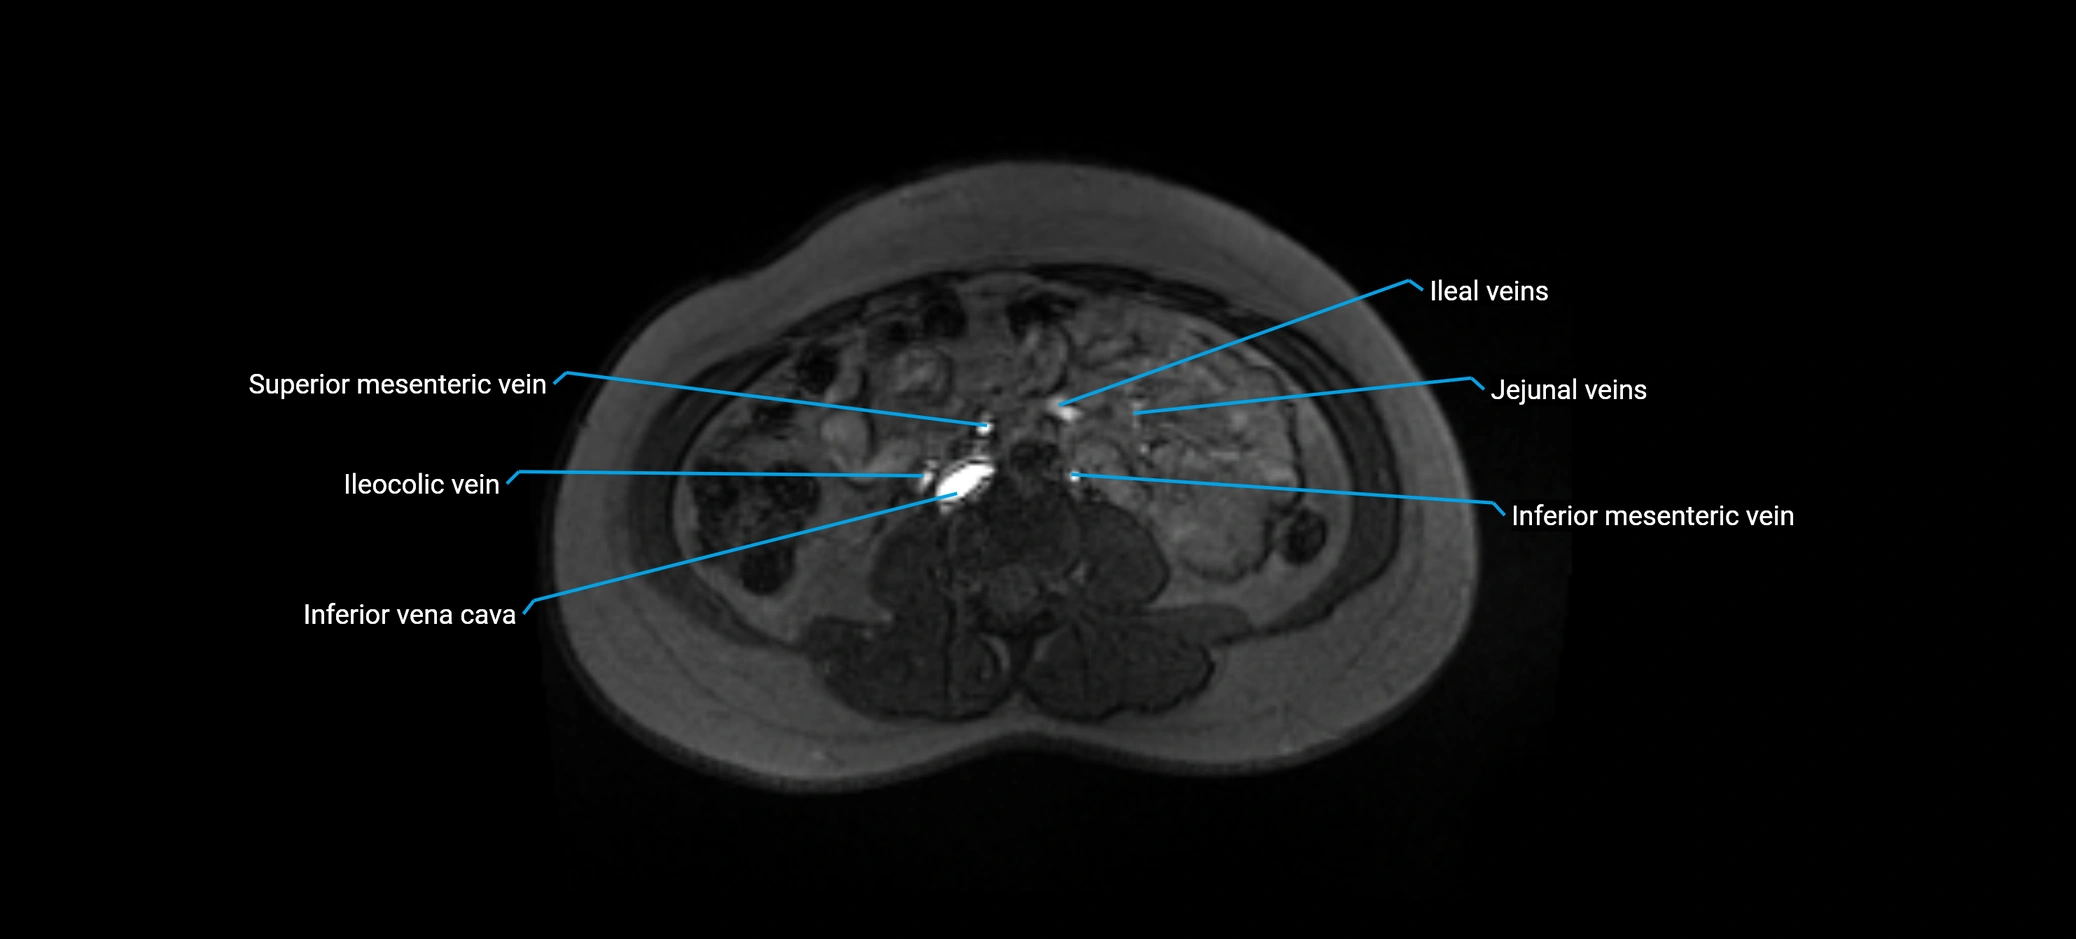

MRI image

image